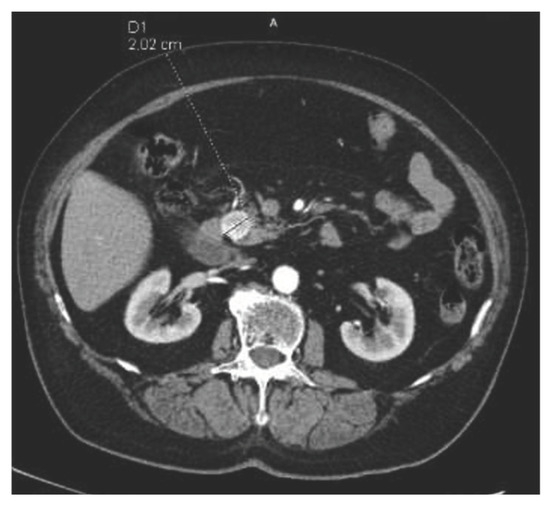

2. First Case